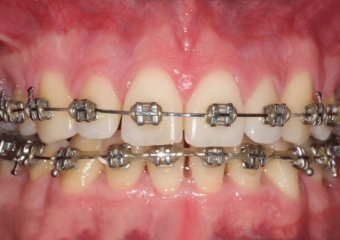

Mordida inicial